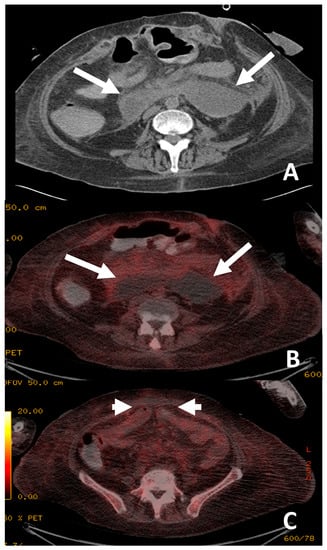

Figure 1. The patient presented with an elevated white cell count and raised C-reactive protein (CRP) of greater than 250 mg/L, but multiple previous image-guided drains, aspirations, line and blood cultures were negative. 18F-FDG PET/CT localised the infective focus to the left peripherally inserted central catheter (PICC) line (white arrow). The PICC line was removed and there was a subsequent improvement in the patient’s clinical condition.

Figure 2. The patient presented with 1 week of pyrexia but no source of infection was identified. Increased uptake was demonstrated in the transplanted stomach (white arrows, image (A)) and small bowel (white arrows, image (B)) suggestive of rejection. Biopsy just prior to 18F-FDG PET/CT demonstrated a non-specific increase in apoptotic debris within the lamina propria of uncertain significance. As no focus of infection was demonstrated and the appearance of the transplanted stomach (A) and small bowel (B) was suggestive of rejection, the patient was treated for rejection with immune suppression. Following anti-rejection treatment, the patient’s clinical picture improved with resolution of the pyrexia. Subsequent biopsies taken 6 weeks later demonstrated no remaining features of rejection.